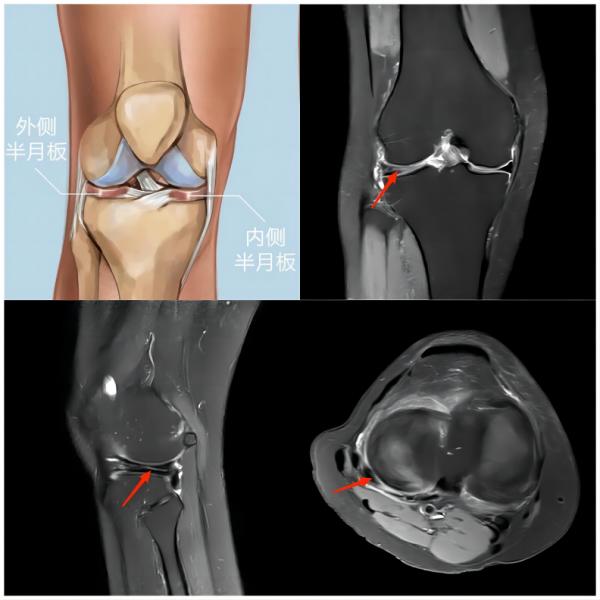

② 膝关节损伤

(上图为右膝外侧半月板撕裂)

常见原因:足球运动中时常发生高频次的急停、冲刺、变向等,并且还会有膝关节的屈伸、外展等动作,这些动作都会增加对膝关节的负荷,从而引发膝关节损伤。主要损伤为半月板体部撕裂、半月板根部撕裂、侧副韧带及交叉韧带的扭伤或撕裂。

(上图为右膝前交叉韧带撕裂)